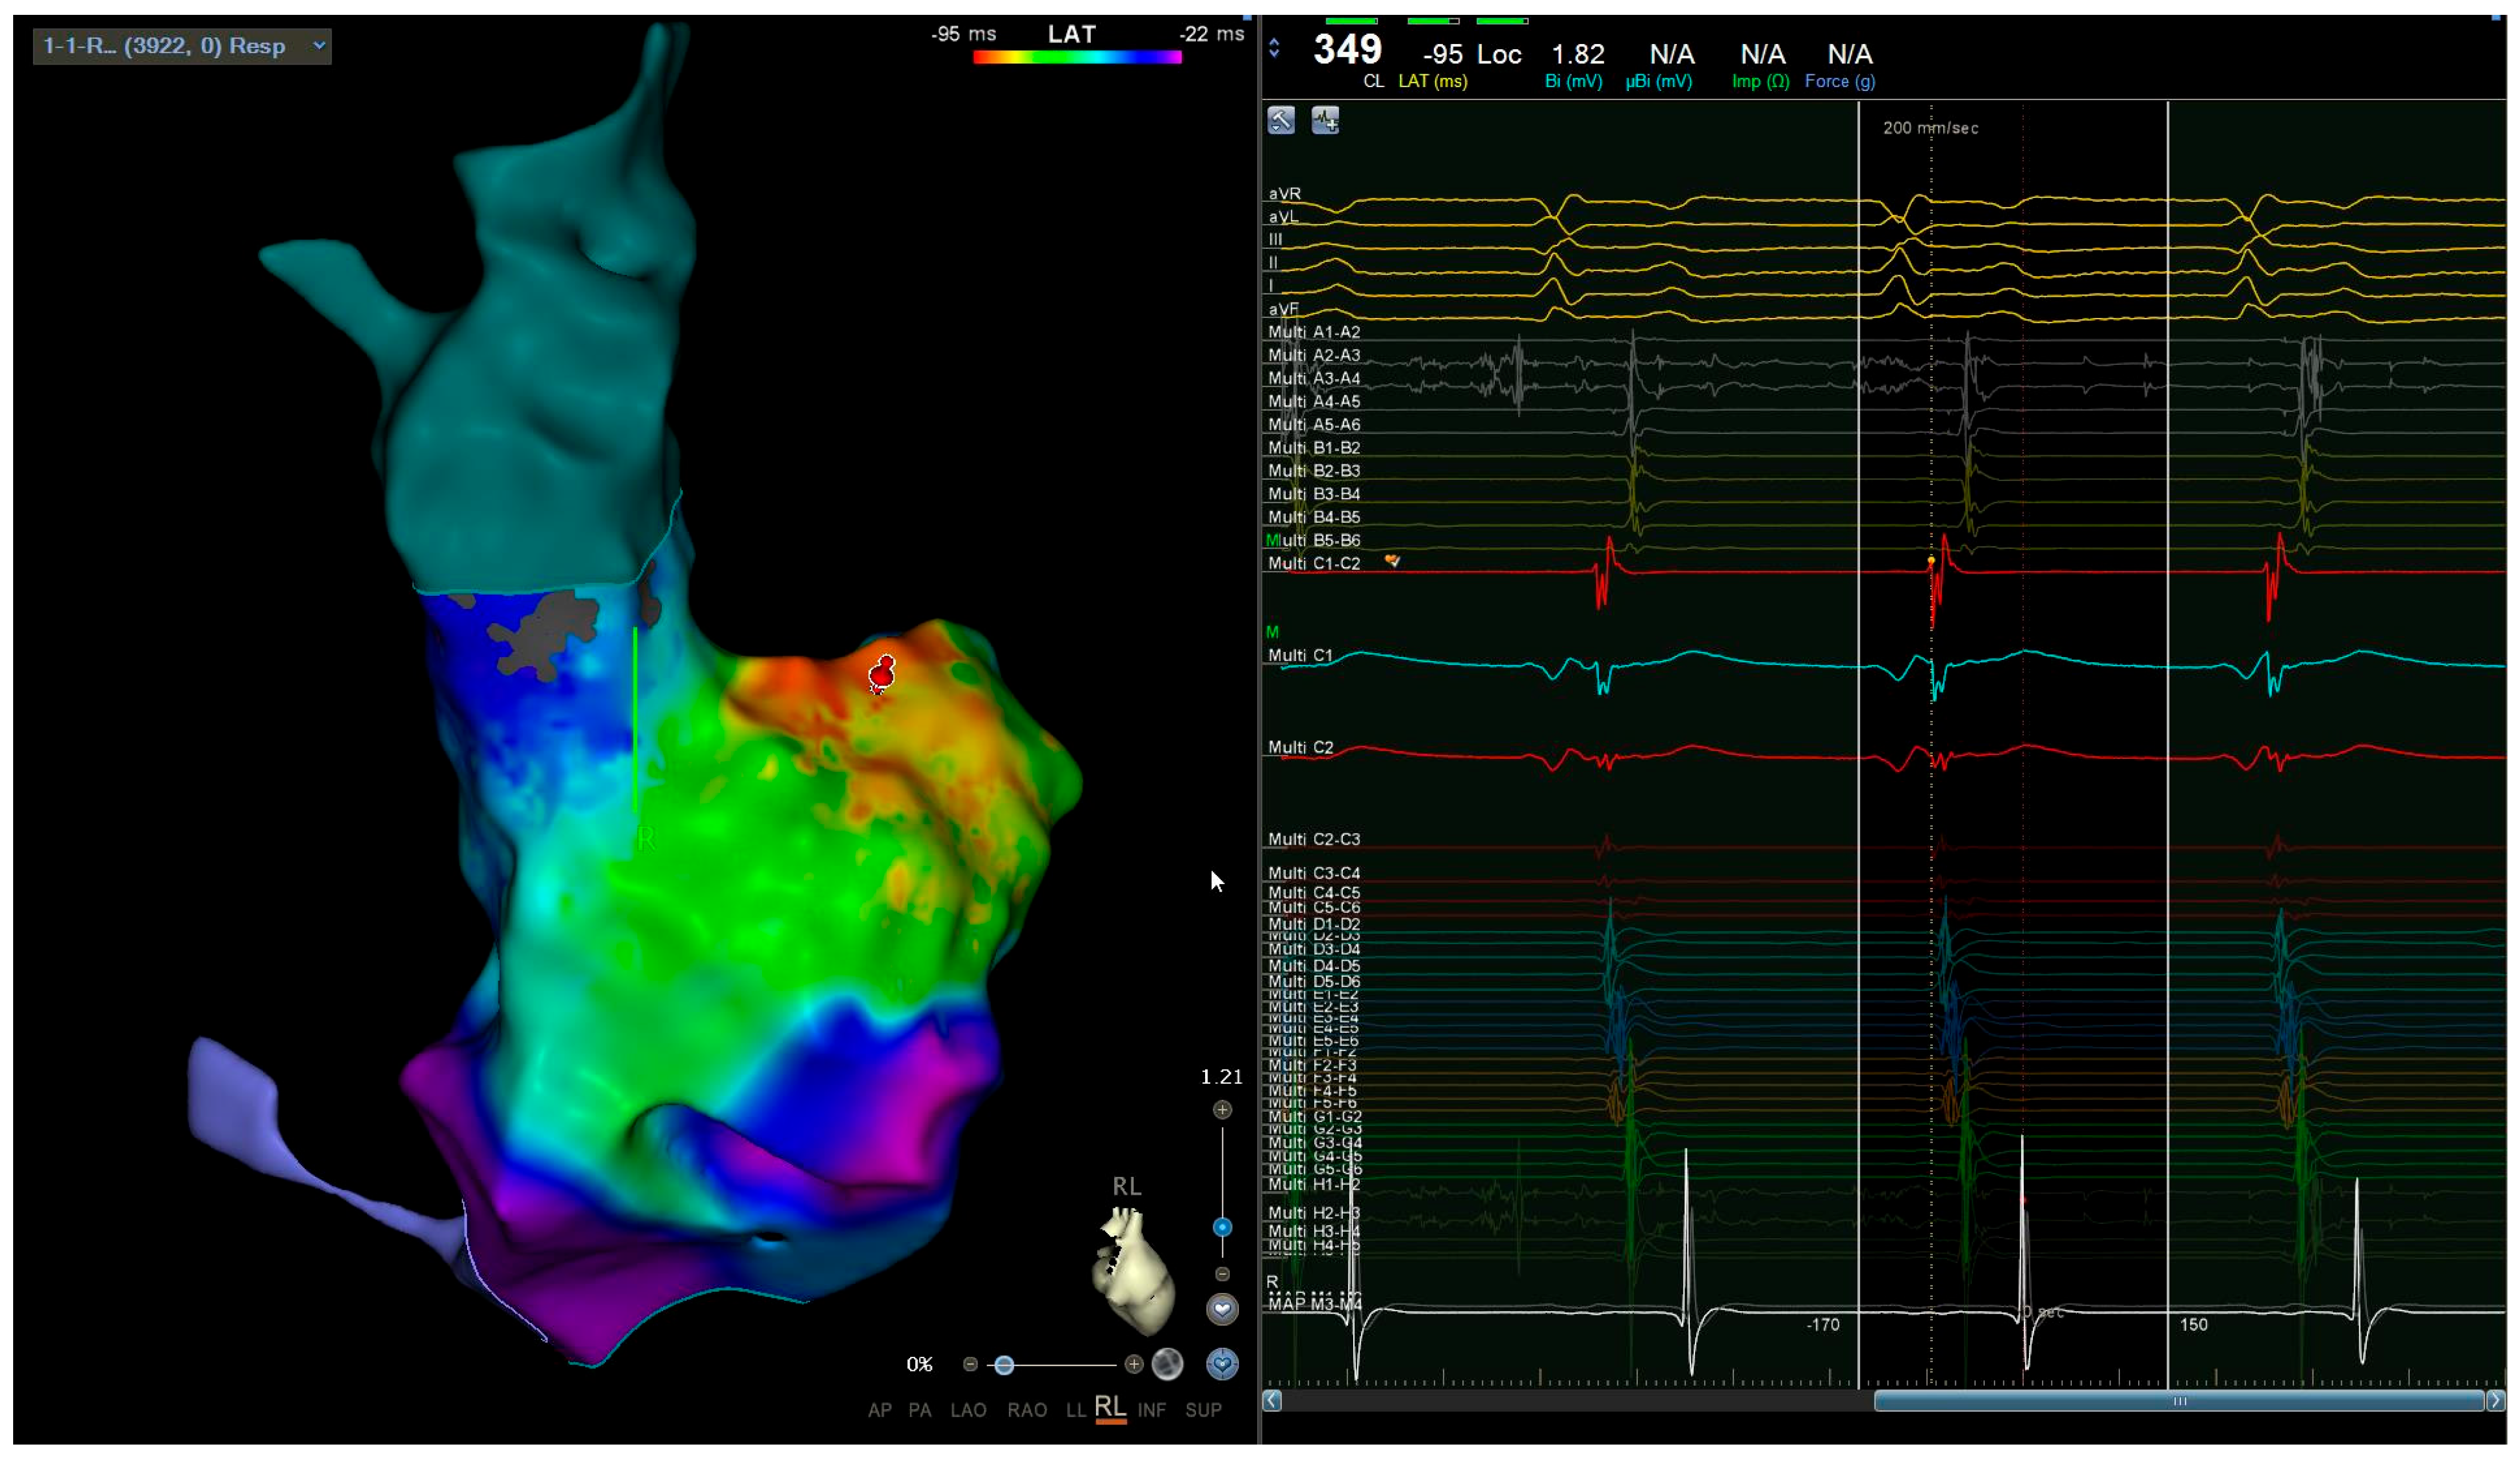

2. Case Description